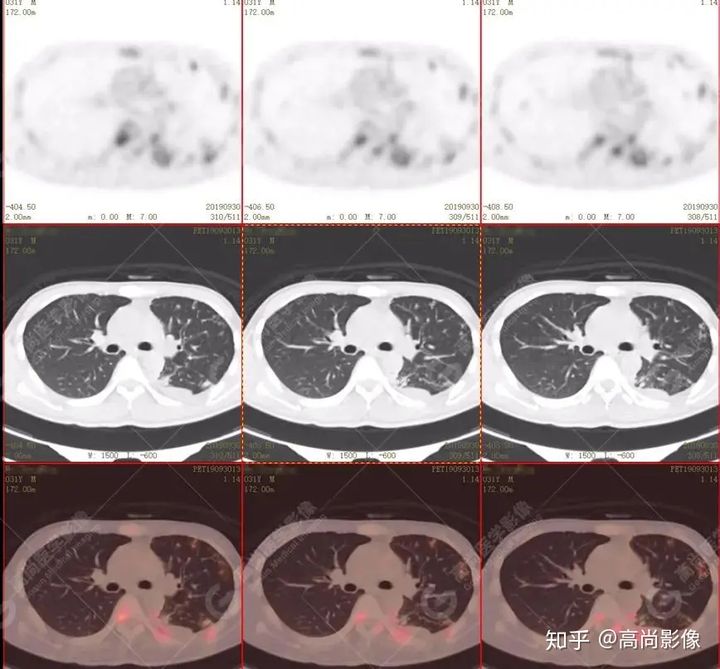

全身多發(fā)高代謝腫大淋巴結(jié),中央代謝缺損

【PET/CT提示】雙肺、左側(cè)胸膜多發(fā)結(jié)節(jié)影,全身多處骨質(zhì)破壞,全身多發(fā)淋巴結(jié)腫大,代謝攝取不均勻性增高。

2.全身多系統(tǒng)、多形態(tài)、多發(fā)病灶(肺部、胸膜、淋巴結(jié)、骨),18F-FDG攝取不均性增高;

特征:肺部病灶簇狀分布,上葉尖段及下葉背段為著;腫大淋巴結(jié)分布不對稱,無融合、中央有壞死改變,與淋巴瘤、轉(zhuǎn)移瘤等有一定的鑒別診斷意義;